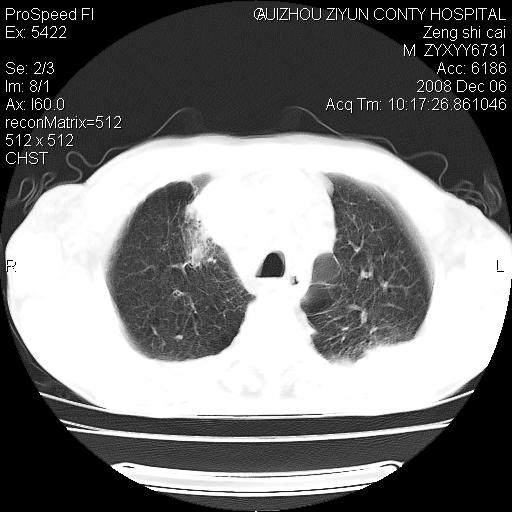

标题: CT16961:M、71岁,咳嗽半年,无血痰;胸片示右肺占位。 [打印本页]

标题: CT16961:M、71岁,咳嗽半年,无血痰;胸片示右肺占位。

右肺癌并纵隔淋巴结及胸膜转移可能性大

右肺癌并纵隔淋巴结及胸膜转移。建议气管镜

右肺纵隔型肺癌伴纵隔淋巴结及胸膜转移!

右肺纵隔型肺癌伴纵隔淋巴结转移!双侧胸水!

1)考虑右肺上叶纵隔型肺癌伴纵隔淋巴结转移。2)心包积液,双侧胸腔积液。

右肺上叶纵隔型肺癌伴纵隔淋巴结转移。心包积液,双侧胸腔积液。

右肺纵隔型肺癌伴纵隔淋巴结转移!双侧胸水\\心包积液

建议强化!主要鉴别是淋巴瘤与肺癌淋巴结转移。